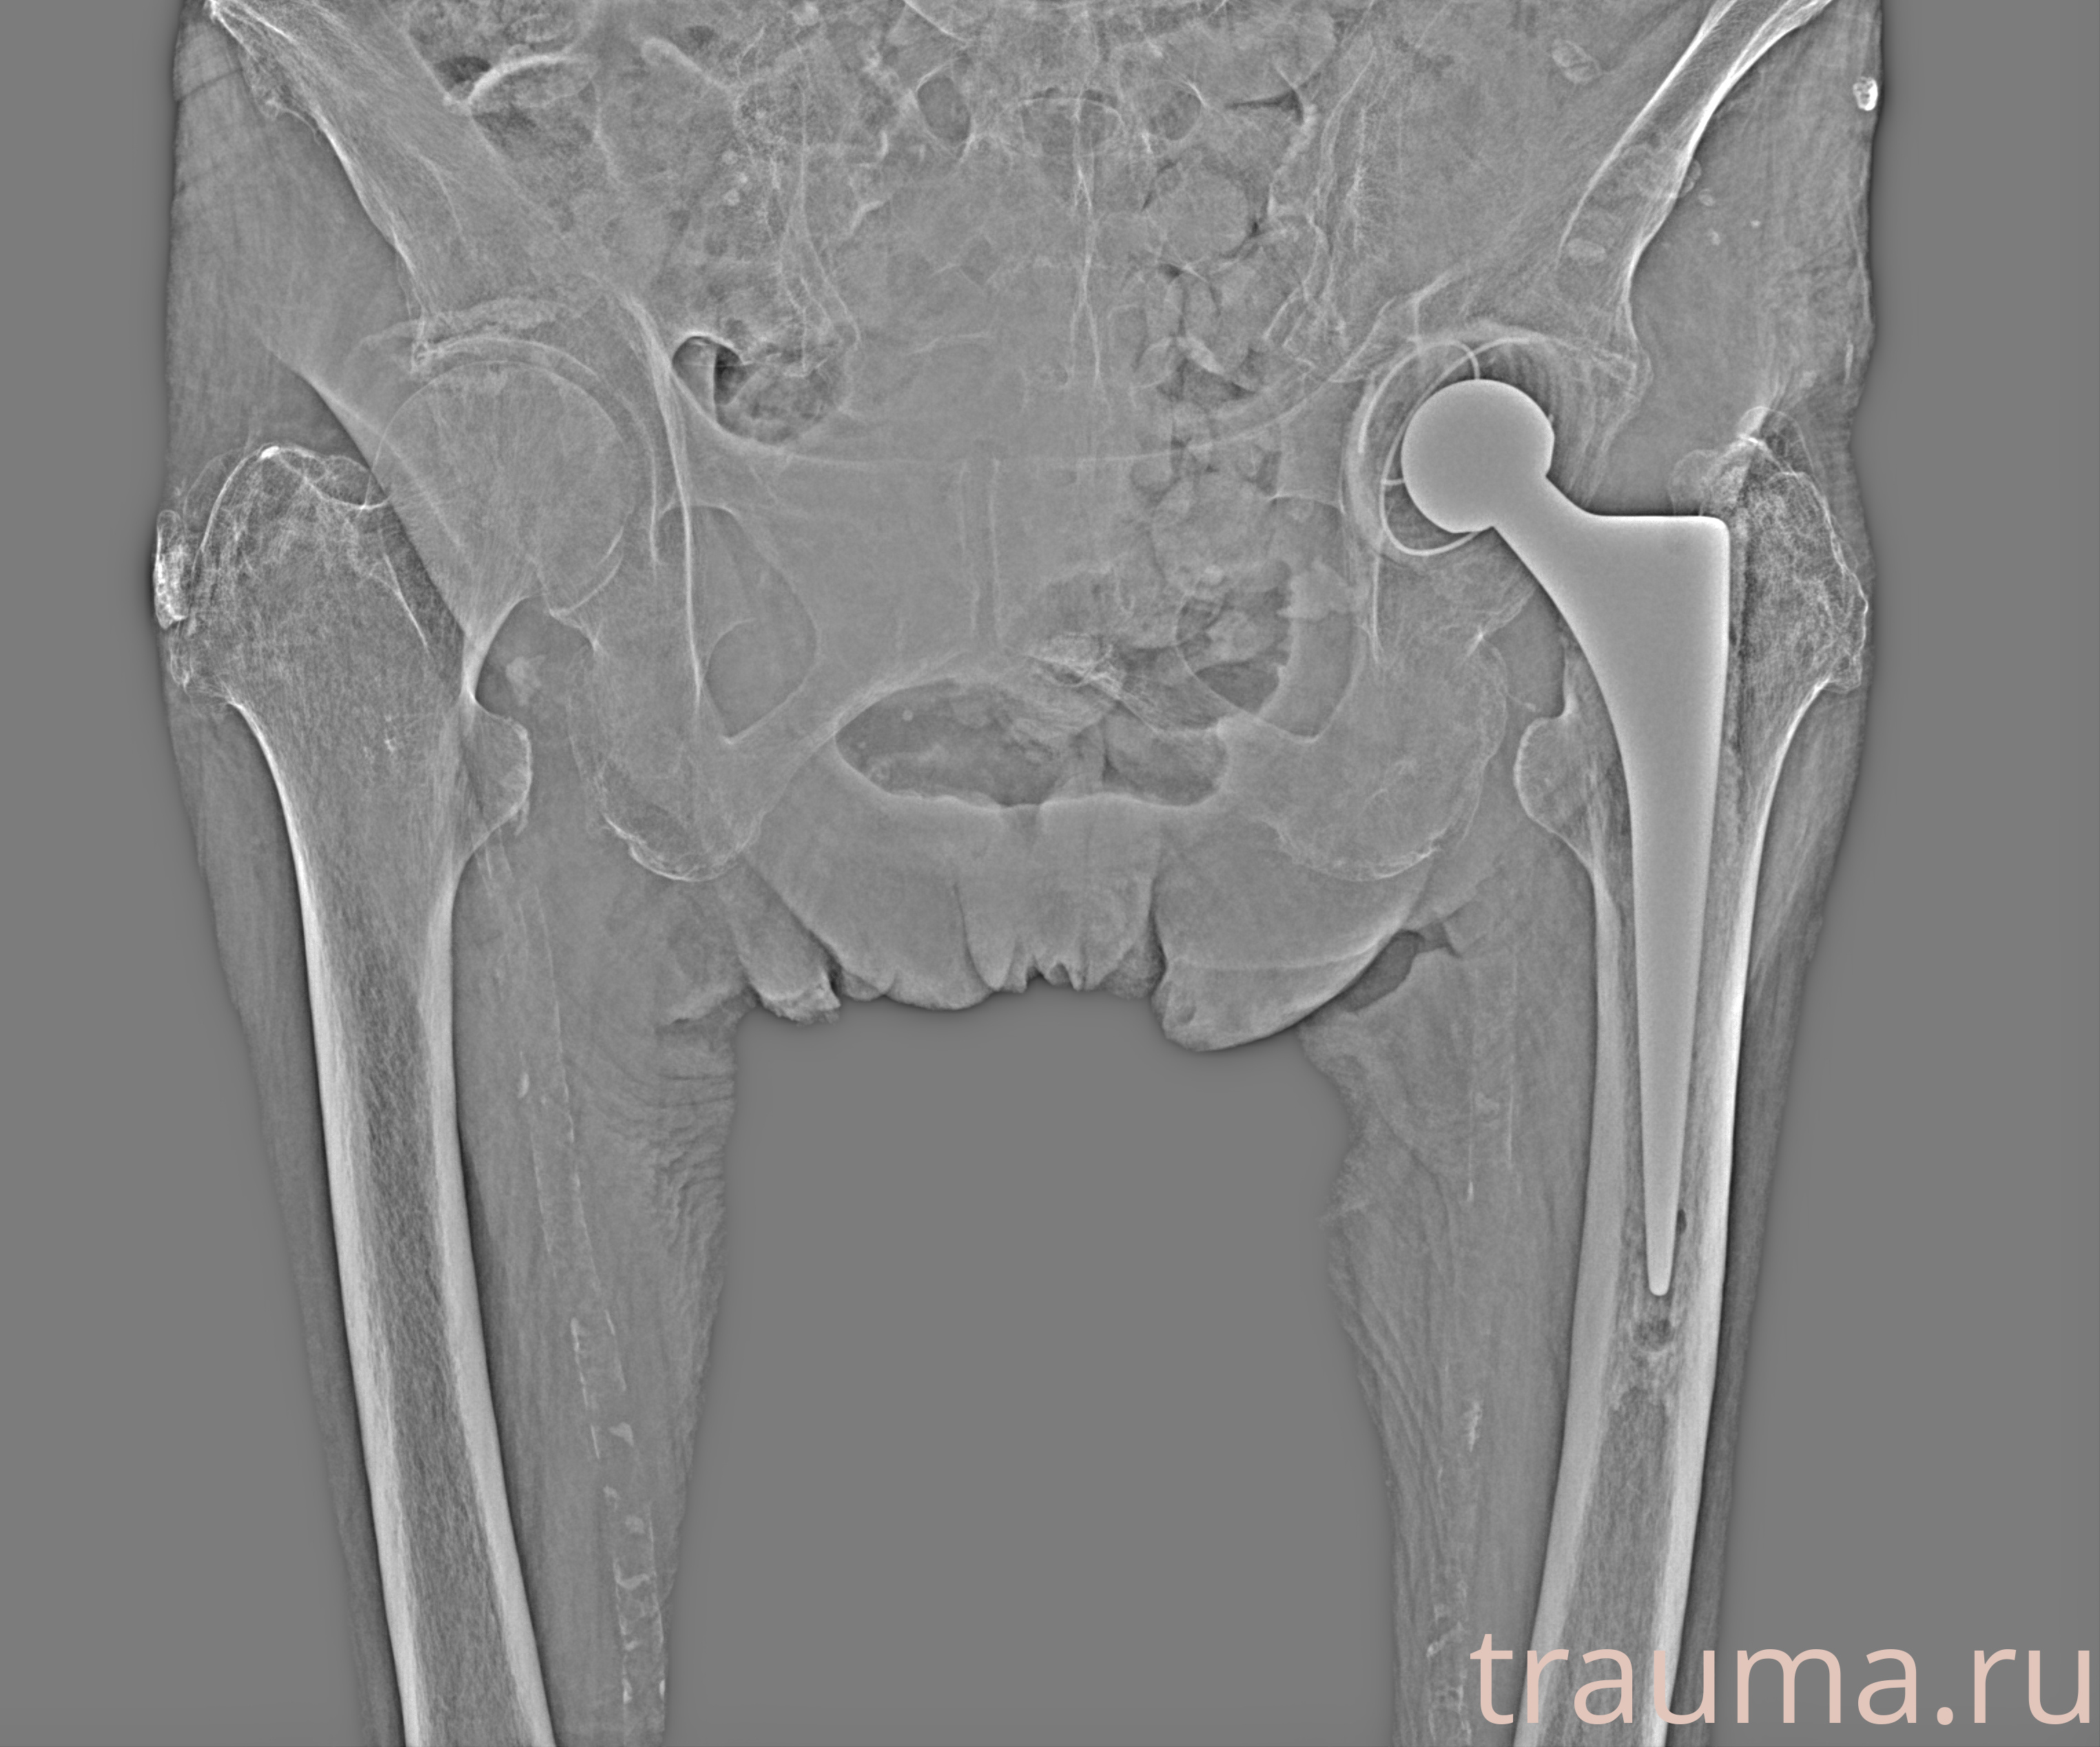

Эндопротез левого тазобедренного сустава